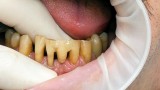

Jedną z popularniejszych metod stabilizacji zębów rozchwianych jest ich szynowanie. Metoda ta, wspierająca inne metody leczenia, jest powszechnie stosowana. Jednym z najnowocześniejszych materiałów wykorzystywanych w stomatologii do szynowania zębów jest taśma poliaramidowa. W opisanym przypadku autorzy pracy przedstawiają sposób uproszczenia całej procedury i ograniczenia ryzyka popełnienia błędu, szczególnie w sytuacji całkowitej utraty zęba. Uzyskano to dzięki zastosowaniu indeksu wykonanego z przezroczystego silikonu.

One of the more popular methods of stabilising loose teeth is to splint them. This method, aiding other methods of treatment, is generally used. One of the most modern materials used in dentistry for splinting teeth, is polyamide tape. In the case described the authors show how to simplify the whole procedure and limit the risk of making a mistake, particularly in the situation of total loss of one tooth. This was achieved thanks to the use of an index made out of transparent silicone.